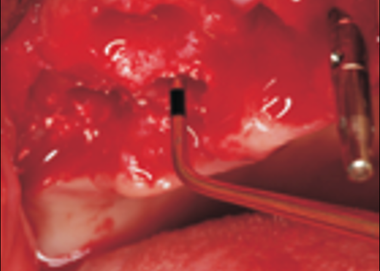

Рассверливание тонкой кортикальной кости дна верхнечелюстного синуса фрезой с ограничителем.